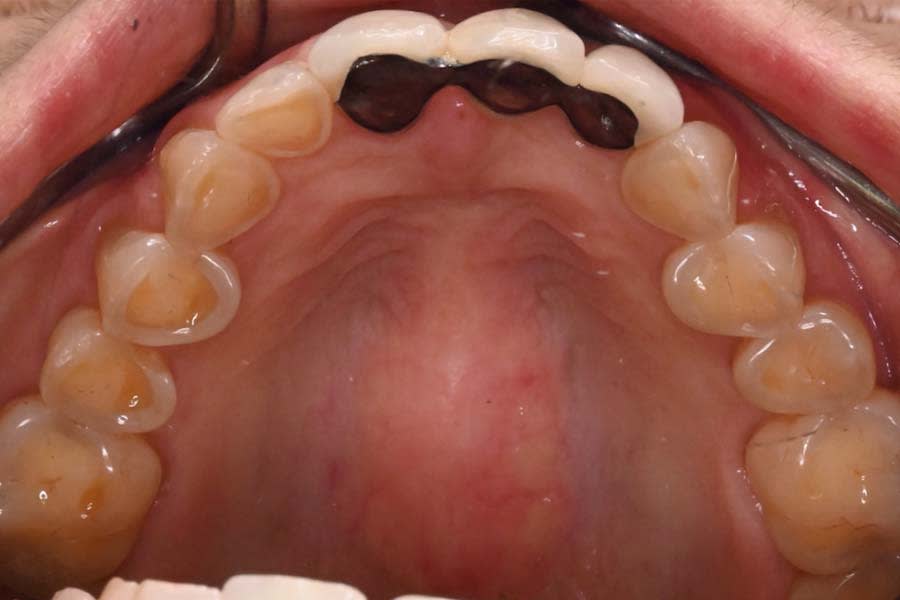

Definitive digital scans of each arch were obtained (Figure 7 and Figure 8), and the definitive restorations were designed based on the diagnostic wax-up (Figure 9). The design files were then exported in standard tessellation language (STL) format and transferred to the in-house technicians for milling of the definitive restorations in lithium-disilicate material. The restorations were subsequently custom-stained and glazed (Figure 10). Based on the patient’s esthetic preferences, modifications were made to the maxillary anterior design before delivery. The definitive restorations were evaluated intraorally and bonded with a luting composite (soft white shade) (Variolink® Esthetic LC, Ivoclar) (Figure 11), with all excess cement carefully removed (Figure 12 and Figure 13). The mandibular incisors were restored with direct composite, and abrasion lesions in the esthetic zone, intended for future root coverage, were provisionally restored with supragingival flowable composite for improved appearance (Figure 14).